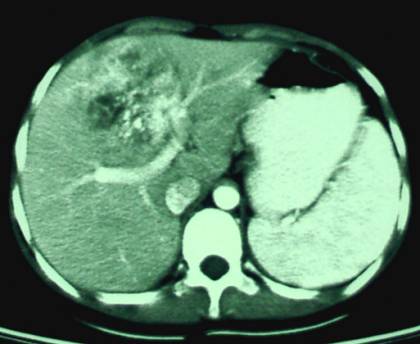

图3:肝右叶肝母细胞瘤的CT 表现 图4:肝右叶肝母细胞瘤的CT表现

图5:肝左叶肝母细胞瘤合并肝内转移

1)平扫:可见肝实性肿块,多由数个结节聚合成大块状,其边缘为高或等密度,中心呈低密度或高低不等密度。

2)增强扫描:在动脉期增强可见多个结节状增强染色征象,门静脉期肿瘤呈低密度,中心有不规则更低密度区域,为肿瘤坏死所致。有的肿瘤内含类似骨组织成分,CT 可显示钙化灶。CT平扫示右肝可见巨块状低密度占位性病变,边缘比较光滑,密度不均,内部可见不规则更低密度区域,其内斑点状钙化。增强示肿瘤可见增强,门静脉期肿瘤呈低密度,中心坏死无增强,肝内胆管扩张。